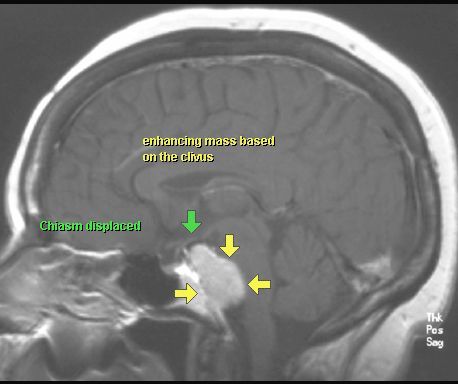

OPONIAK

MRI